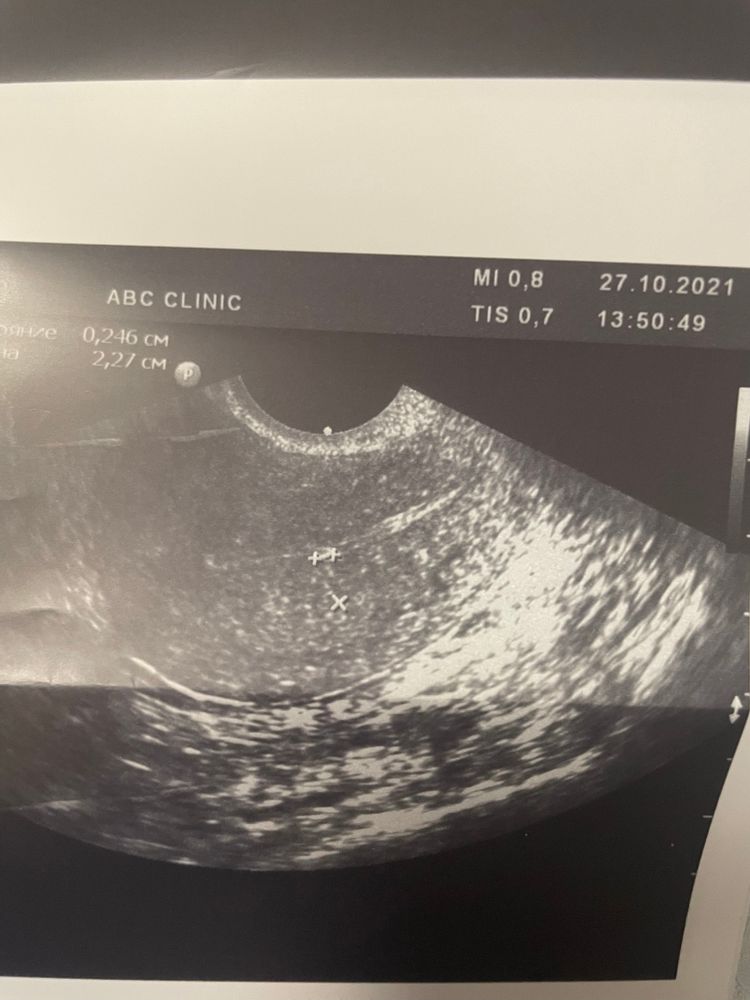

а второй вопрос , она увидела в правом яичнике фолликулярную кисту 4 см, не лопнул фоллик ( обычно у меня овуляции свои .. при такой кисте можно планировать в этом цикле ? Или ждать когда уйдёт ? мне 41 каждый цикл на счету 😒😒😒

Вообще похоже на полип. И он не даст Б. Давай третье УЗИ дождёмся, но я уверена, что это полип. На снимке у меня такой же был. И размер само то для начала его роста. Киста рассосётся, тогда новый ДФ вырастет.

Виктория Север, я тоже считаю полип , пойду после локдауна записываться в врачу и гистеру просится , я тоже сравниваю свой прошлый полип и этот вроде так же выглядит , но размер в пять раз меньше и за два месяца он не вырос 2-3 мм .. врач говорит не помешает он .. на самом деле рубцы полипы складки в эндометрии, эндометриоз выглядят на узи как белое что то , почти одинаково